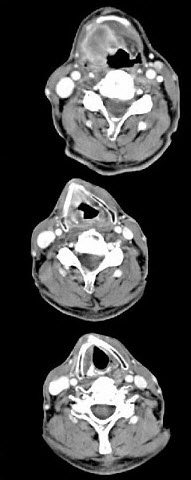

男,63岁,咽喉部不适约一年,近2个月经常咳嗽,痰中带有血丝,CT如图所示,应诊断为()。

A、梨状窝癌

B、声门型喉癌

C、声门下型喉癌

D、声门上型喉癌

E、混合型喉癌

正确答案:

D